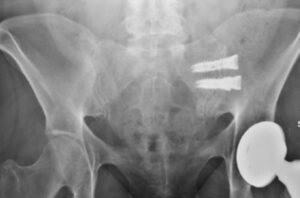

iFuse Bedrock Granite not available outside the US